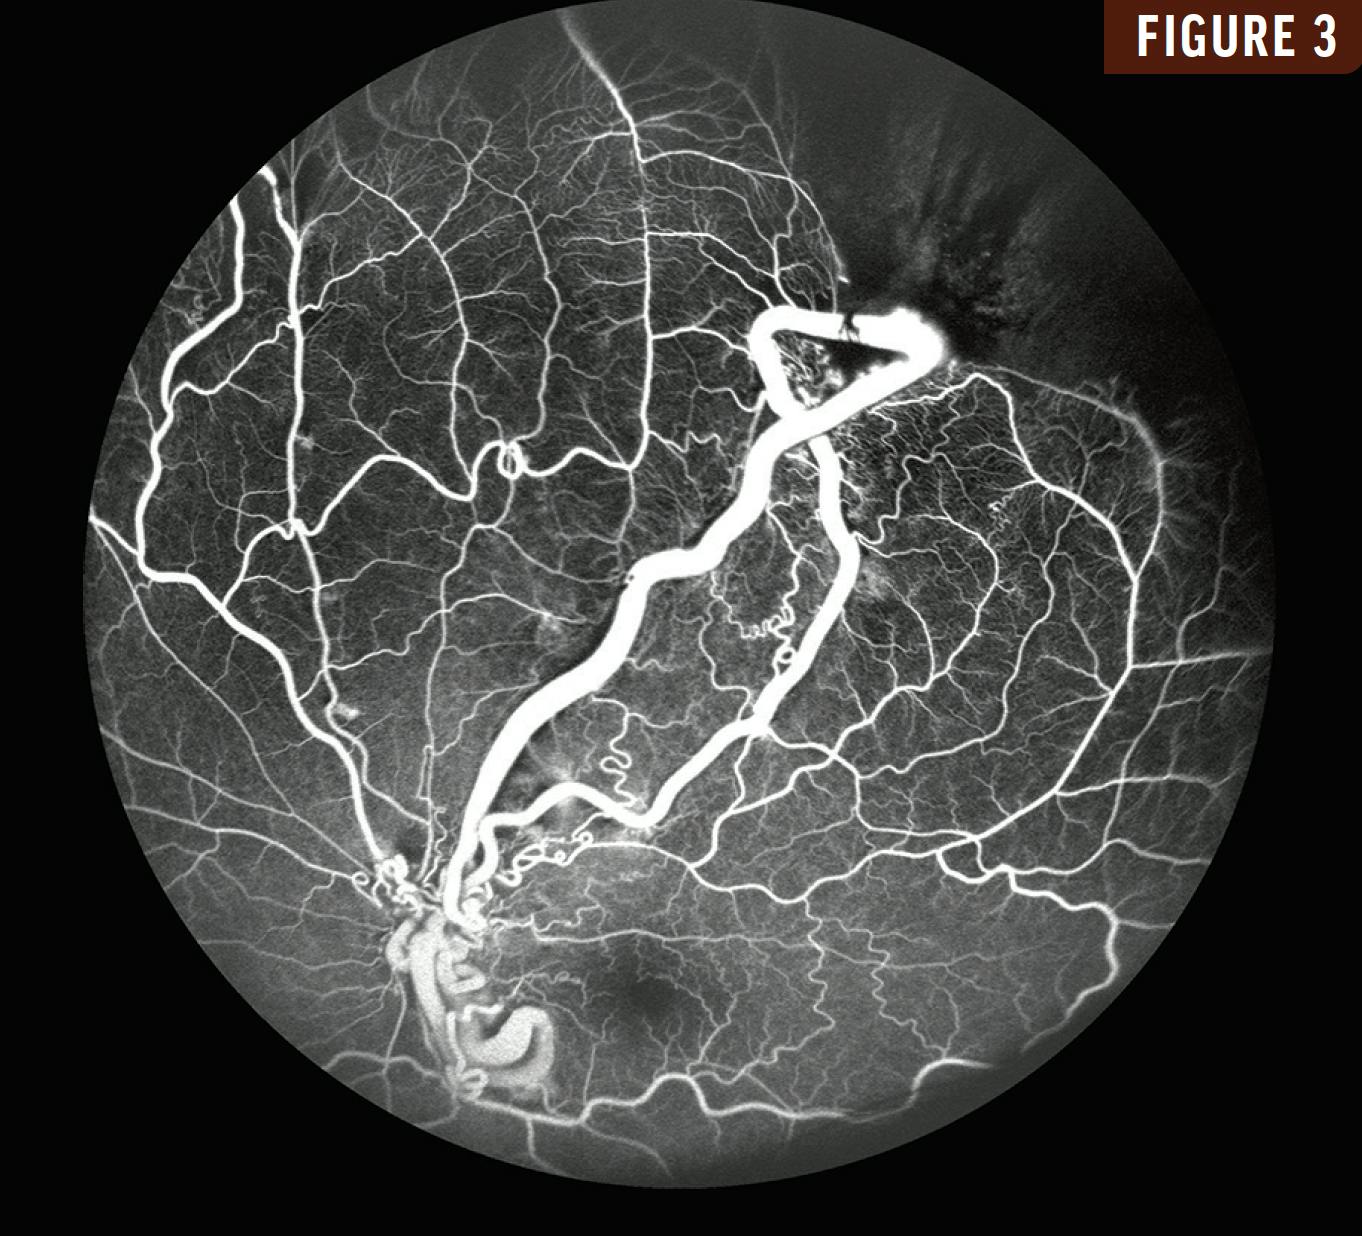

A 10-year-old girl presented with a 3-month history of reduced vision in her left eye. Her VA was 20/20 OD and 20/200 OS. Fundus examination of her left eye revealed markedly dilated, corkscrew-like arteriovenous channels with perivascular sheathing that extended from the optic disc into the superotemporal retina (Figure 1). OCT revealed large hyperreflective intraretinal vessels with posterior shadowing and a normal foveal contour (Figure 2). Fluorescein angiography revealed rapid filling of the arterial and venous components with minimal transit time with no associated leakage (Figure 3).